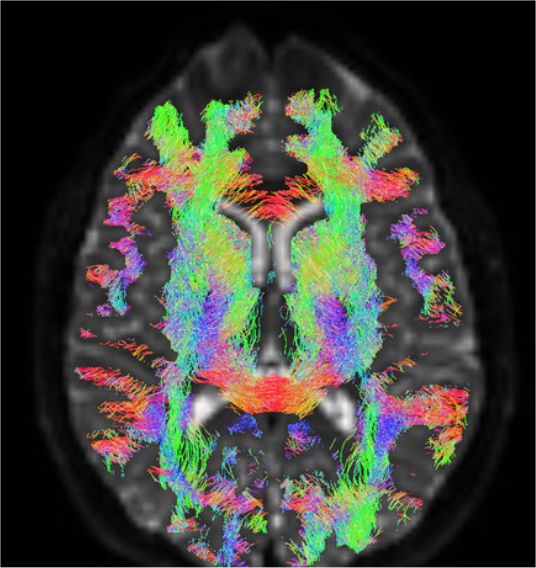

Resultado de una tractografía. (Foto: A. Planchuelo)

La información que aportan estos resultados no se desprende de la visualización de las imágenes en sí, sino de su procesado posterior. En el análisis de la conectividad estructural, este equipo también ha sido pionero en aplicar al estudio de la migraña la técnica conocida como tractografía, que permite investigar los tractos de sustancia blanca o fibras que discurren por el sistema nervioso, para analizar directamente las conexiones entre regiones de sustancia gris.